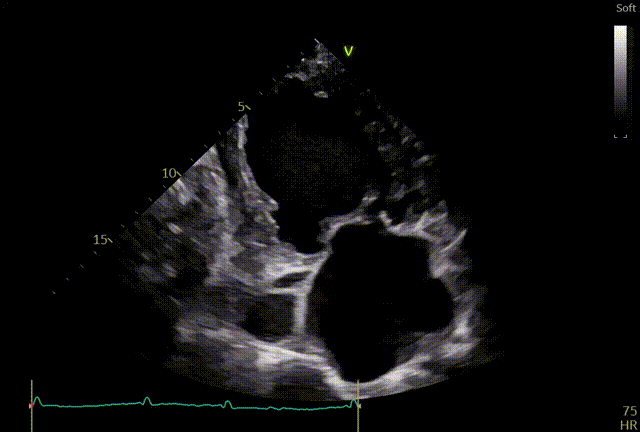

术前TTE

两腔心

短轴

四腔心zoom模式

反流情况